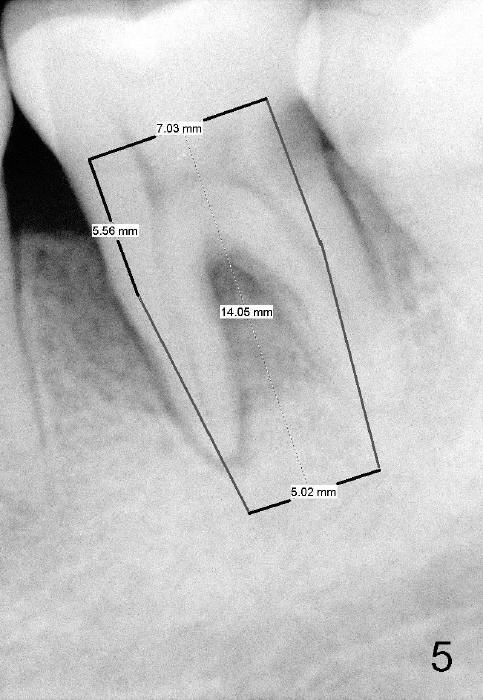

A 48-year-old lady has poor dentition. Four years and a half ago when the tooth #21 needed root canal therapy (RCT), the tooth #19 showed bone loss (Fig.1 arrowheads) and hidden caries (white *). The carious lesion caused severe toothache 2 years later (Fig.2 *), while the perio lesion remain severe. The tooth #19 received RCT; the patient remained asymptomatic until recently. Since the patient is satisfied with immediate implant with the tooth #2 (mainly perio lesion), she is not hesitant in accepting the same mode of treatment for #19.

Considering severe bone resorption, a 6.9x10 mm bone-level (Fig.4) or 7x14 mm gingiva-level (Fig.5) implant does not seem to be long enough to achieve primary stability. Probably a 7x17 mm gingiva-level implant is more appropriate, but it carries more risk of nerve injury. Be careful. Take several intraop PAs for depth confirmation. Try shorter osteotomy and implant first and use longer one if necessary.